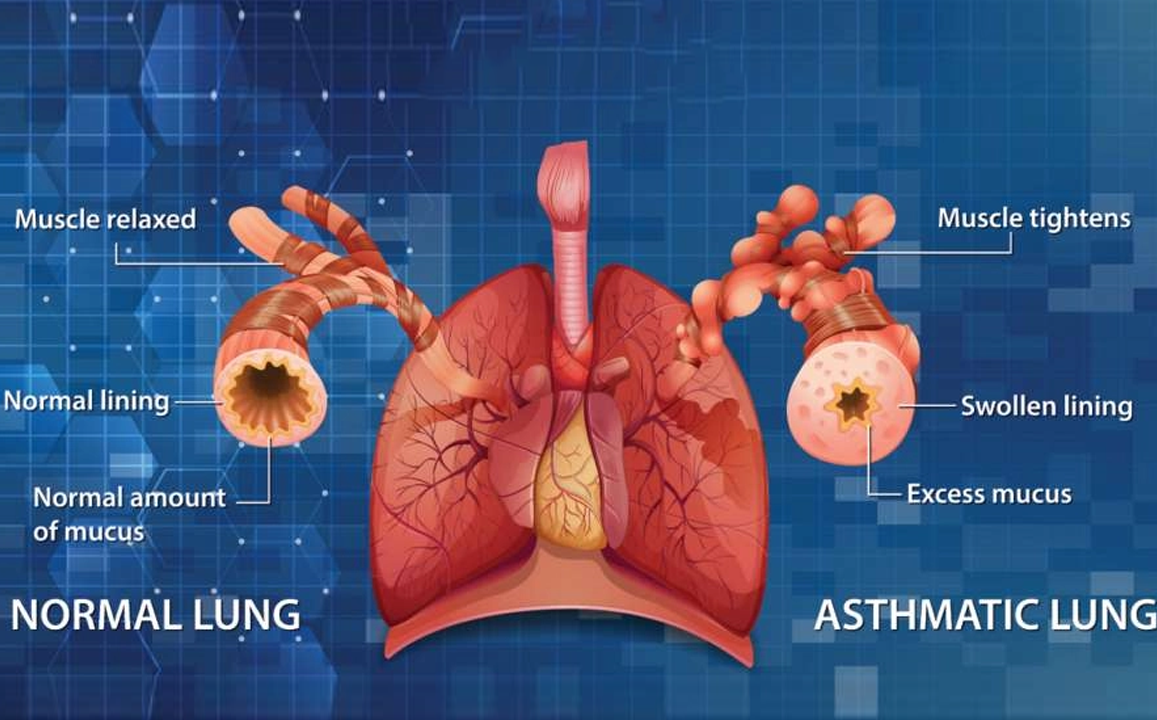

Asthma

Asthma is a chronic respiratory condition causing airway inflammation, leading to difficulty breathing, wheezing, coughing, and chest tightness.